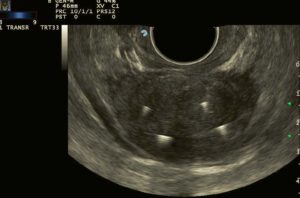

Caso Clinico n.1

Paziente affetto da IPB, con volume basale di 64 ml è stato trattato con Termoablazione con EchoLaser con due fibre per lobo.

Immagine ecografica pre trattamento

Immagine ecografica post trattamento a 4 mesi di follow-up

Il controllo di follow-up a 4 mesi dal trattamento ha evidenziato:

- una riduzione volumetrica da 64 ml a 37 ml

- residuo post-minzione da 200 ml a 43 ml

- IPSS score da 29 a 10

- Quality of Life (QoL) score da 5 a 1

- Massima velocità del flusso da 4 ml/s a 14 ml/s

- Assenza di complicazioni

Immagini per gentile concessione del Dott. Patelli (Ospedale Pesenti Fenaroli, Alzano Lombardo)